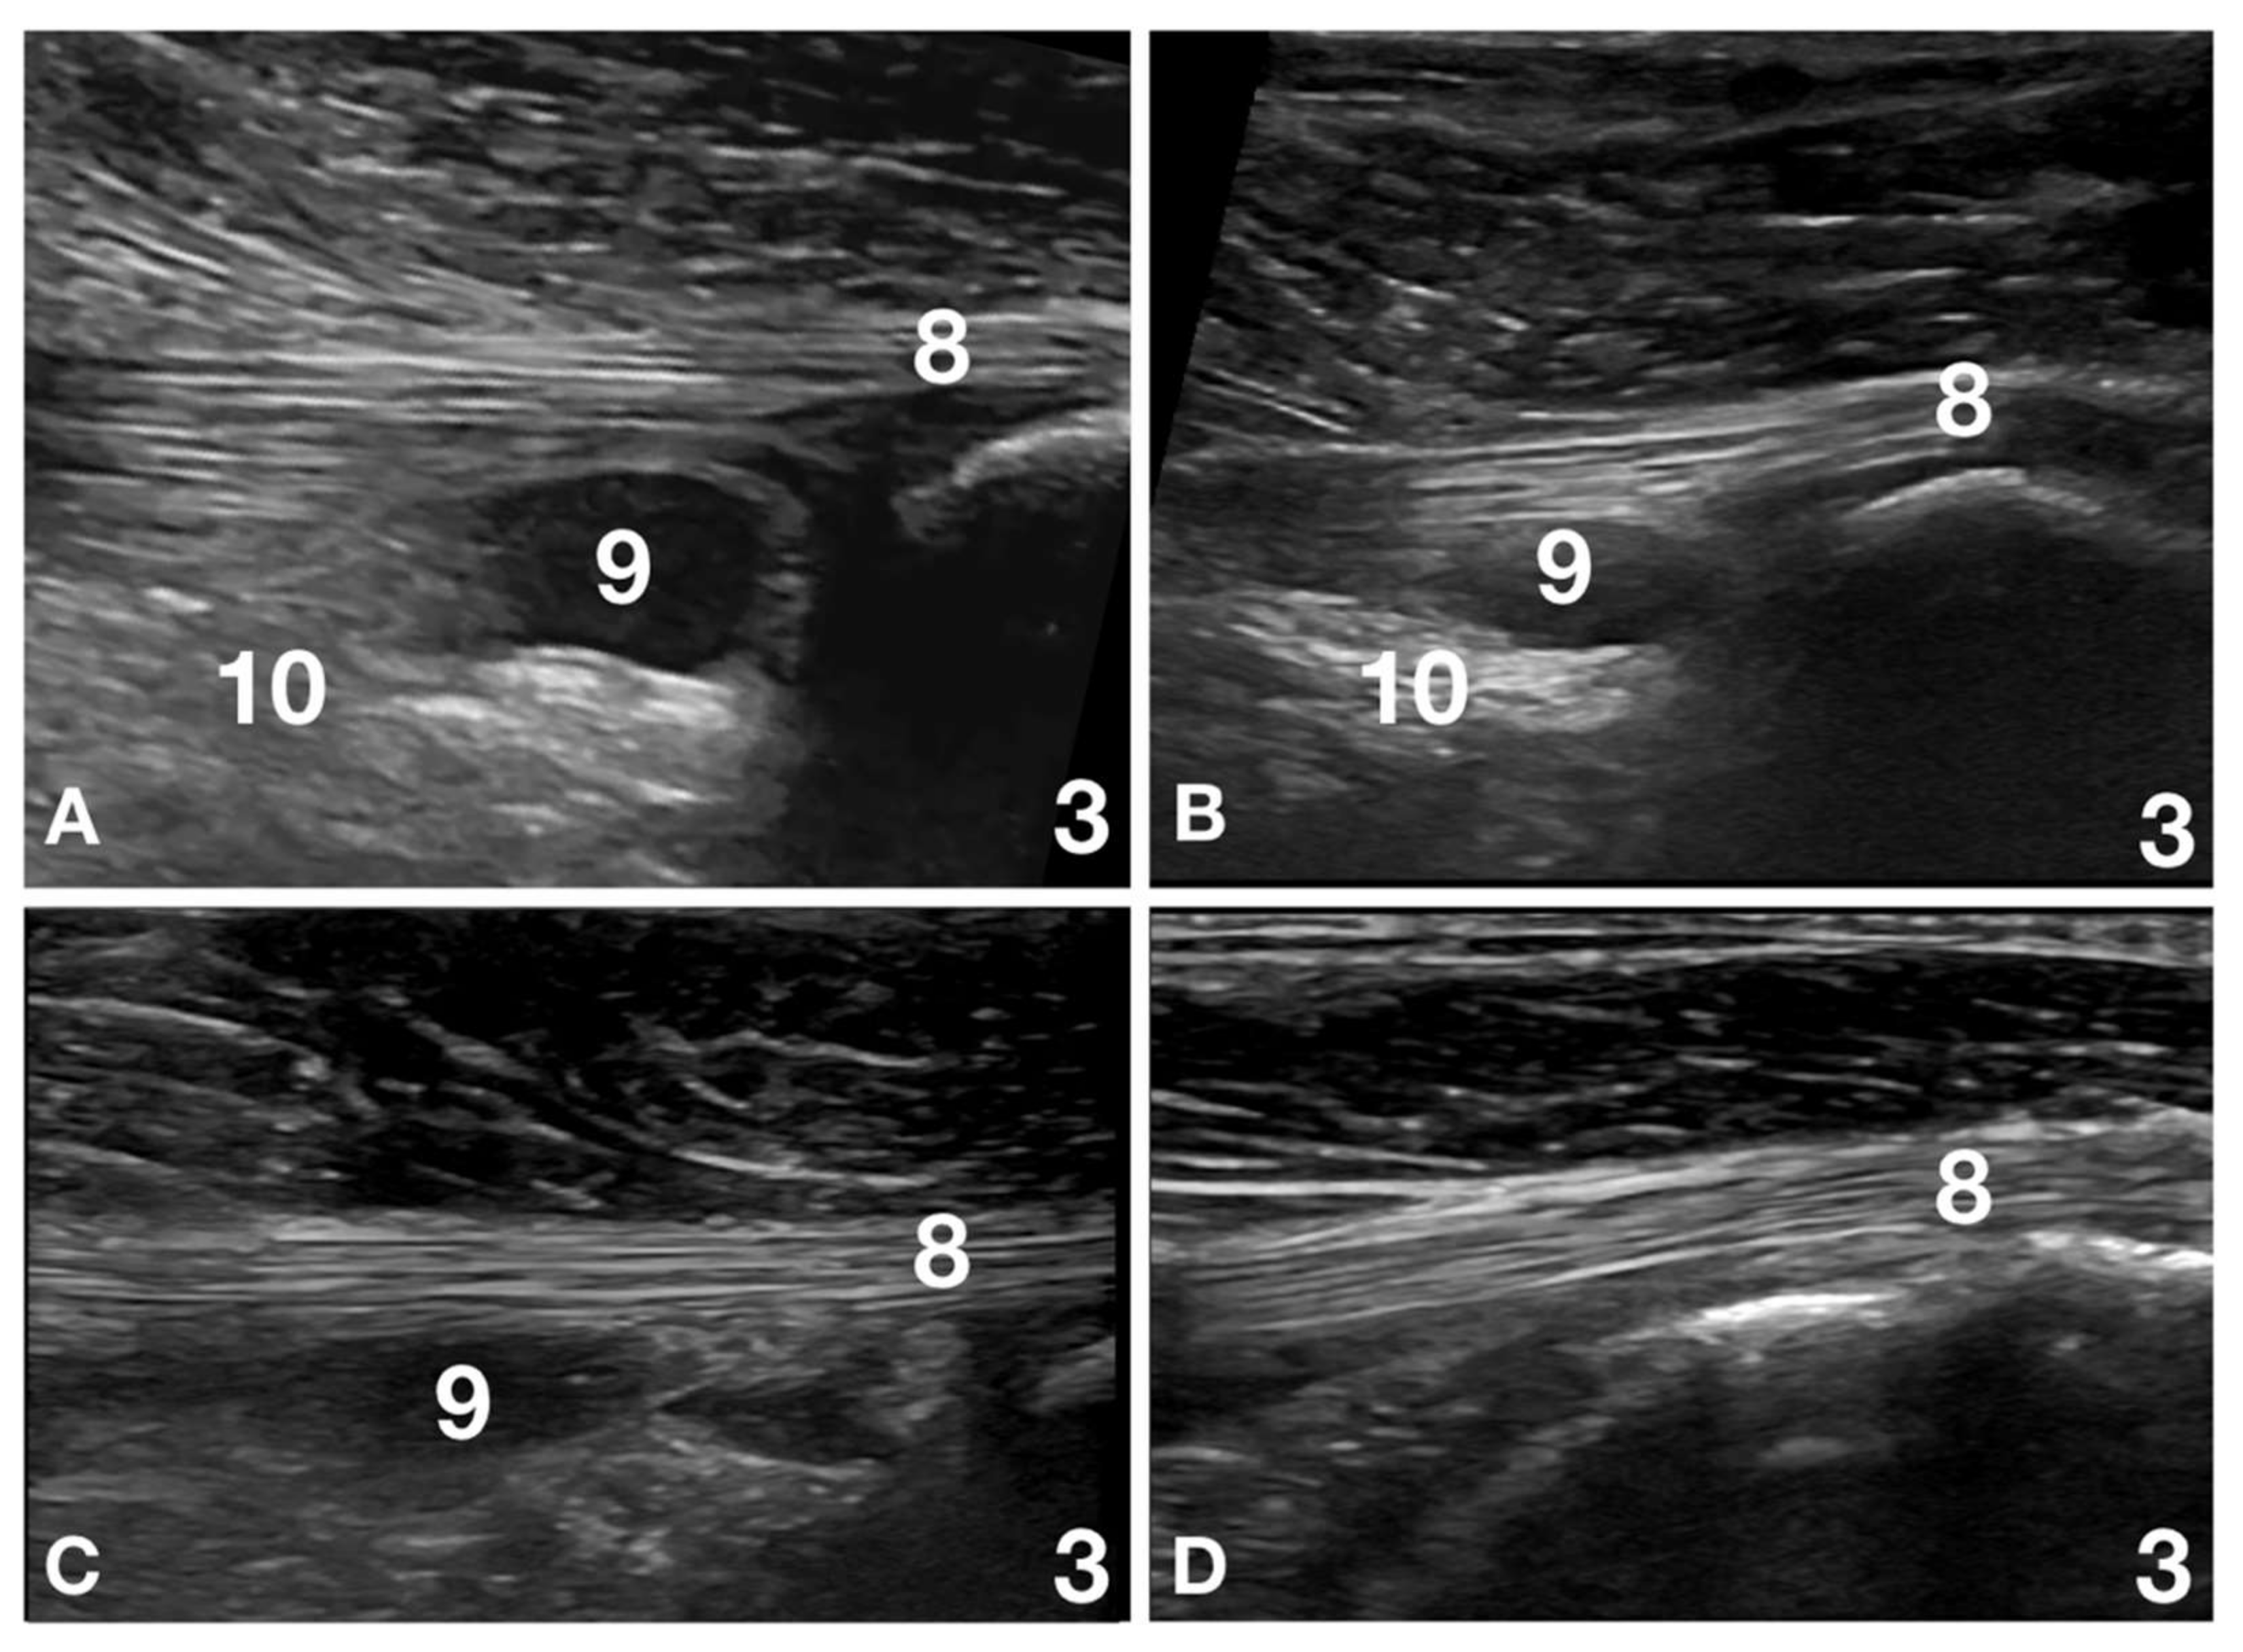

In one patient, adhesion of the joint capsule with an altered supraspinatus tendon was seen, not associated with changes in the adjacent biceps tendon. In three patients (3/32; 9%), including those previously mentioned, an isolated supraspinatus lesion, considered clinically relevant, was the most important finding. In four patients (4/32; 12%), the most relevant finding was a partial rupture and thinning of the infraspinatus tendon and, in two patients (2/32; 6%), and an associated muscle rupture was present (Figure 3).

Figure 3.

Images of the left shoulder at the level of the infraspinatus muscle and tendon insertion of patient number 18 at Time 0, Time 2, Time 4 and Time 6 are reported. (A) Time 0: the infraspinatus tendon (8) is thin and relatively ill-defined at its humeral insertion (3). A large anechoic area (9) surrounded by scattered artefacts (10) is seen in the region of the teno-muscular junction. This lesion was considered a muscle rupture and was differentiated by an enlarged infraspinatus bursa due to the size, location and scattered artefacts associated with acute inflammation. The severe pain at palpation of the region was another element that helped to differentiate the pathology from normal anatomy. (B) Time 2: the infraspinatus tendon (8) is thin as compared with the contralateral limb but is better defined with a more pronounced fibrillar pattern. The anechoic area (9) is reduced in size, and the associated scattered artefacts (10) are also reduced. Mild pain was still present on palpation. (C) Time 4: the infraspinatus tendon (8) has nearly the same diameter as the contralateral limb. The fibrillar pattern is compact and shows good alignment. The anechoic area (9) is reduced in size, more difficult to see, lacks well-defined margins, and is not associated with scattered artefacts. No pain was present on palpation. (D) Time 6: the infraspinatus tendon (8) shows the same diameter and fibrillar pattern as the contralateral limb. The anechoic area (9) is no longer visible and is not associated with scattered artefacts. No significant differences with the contralateral limb are visible. No pain was present on palpation.